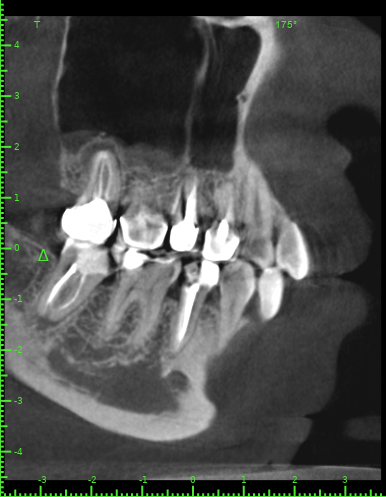

Katya88 Опубликовано 28 июля, 2021 Поделиться Опубликовано 28 июля, 2021 Мой стоматолог терапевт советует удалить, так как там кисты, а ортопед советует найти того, кто займется лечением. КТ прилагаю https://drive.google.com/file/d/1Z-neEH63BszTXxa8bAOG1tgsrIrsqrVK/view?usp=drive_web Ссылка на комментарий

Женька Опубликовано 28 июля, 2021 Поделиться Опубликовано 28 июля, 2021 2.6 2.7 3.7 На 3.5 и 1.5 стоит обратить внимание 1.5 1 Ссылка на комментарий

Женька Опубликовано 28 июля, 2021 Поделиться Опубликовано 28 июля, 2021 54 минуты назад, Katya88 сказал: 1.5 менять коронку как минимум снять существующую конструкцию и посмотреть клинически на зуб(ы). 1.5 на КТ выглядит удручающе. По остальным, я бы поддержал ортопеда и попытался зубы сохранить. Пусть коллеги меня поправят. 1 1 Ссылка на комментарий